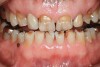

Figure 1  Classic presentation of the bruxism triad. Lateral wear pattern, generalized buccal tooth loss from erosion and abrasion, and history of sleep disruption.

Figure 1